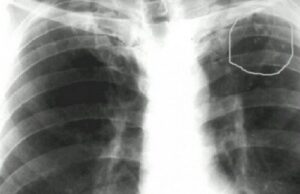

Что такое метатуберкулезные изменения в легких

Метатуберкулезные изменения в легких возникают в результате замещения органа соединительной тканью. Часто они не имеют клинических симптомов и поэтому обнаруживаются при рентгенологическом исследовании. Чтобы выяснить причину изменений, необходимо пройти обследование у фтизиатра, после чего специалист подберет соответствующую тактику лечения, чтобы не допустить развития дыхательной недостаточности. Что это такое? Метатуберкулиновые поражения в легких — это заболевание, …